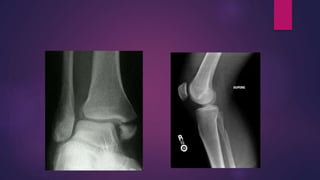

BOSWORTH FRACTURE

DISLOCATION

 Fracture of the distal fibula with an

associated fixed posterior dislocation of

the proximal fragment which becomes

trapped behind the posterior tibial

tubercle.

 Severe external rotation of the ankle

POTT’S FRACTURE

 A common term for bimalleolar

fracture.

 In the Pott fracture, the fibula is

fractured above the intact distal

tibiofibular syndesmosis, the

deltoid ligament is ruptured, and

the talus is subluxed laterally